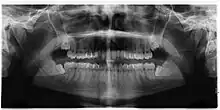

If the tooth cannot be assessed with clinical exam alone, the diagnosis is made using either a panoramic radiograph or cone-beam CT. Where unerupted wisdom teeth still have eruption potential several predictors are used to determine the chance of the teeth becoming impacted. The ratio of space between the tooth crown length and the amount of space available, the angle of the teeth compared to the other teeth are the two most commonly used predictors, with the space ratio being the most accurate. Despite the capacity for movement into early adulthood, the likelihood that the tooth will become impacted can be predicted when the ratio of space available to the length of the crown of the tooth is under 1.[5]: 141

There is no standard to screen for wisdom teeth. It has been suggested, absent evidence to support routinely retaining or removing wisdom teeth, that evaluation with panoramic radiograph, starting between the ages of 16 and 25 be completed every 3 years. Once there is the possibility of the teeth developing disease, then a discussion about the operative risks versus long-term risk of retention with an oral and maxillofacial surgeon or other clinician trained to evaluate wisdom teeth is recommended. These recommendations are based on expert opinion level evidence.[19] Screening at a younger age may be required if the second molars (the "12-year molars") fail to erupt as ectopic positioning of the wisdom teeth can prevent their eruption. Radiographs can be avoided if the majority of the tooth is visible in the mouth.